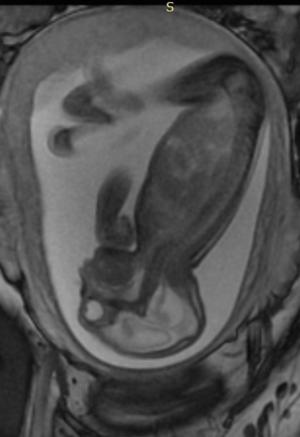

In a third study, ultrasound and fetal MRI were performed on pregnant patients with Zika virus infection at different gestational ages. Once the babies were born, they underwent ultrasound, CT and MRI. The researchers then created 3-D virtual and physical models of the skulls. More than half the babies had microcephaly, brain calcifications and loss of brain tissue volume, along with other structural changes.

"The emergence of Zika virus in the Americas has coincided with increased reports of babies born with microcephaly," said study author Heron Werner Jr., M.D., Ph.D., from the Department of Radiology at Clínica de Diagnóstico por Imagem. "An early diagnosis may help in treating these babies after birth. Moreover, the knowledge of abnormalities present in the central nervous system may give hints about the pathophysiology of the disease."